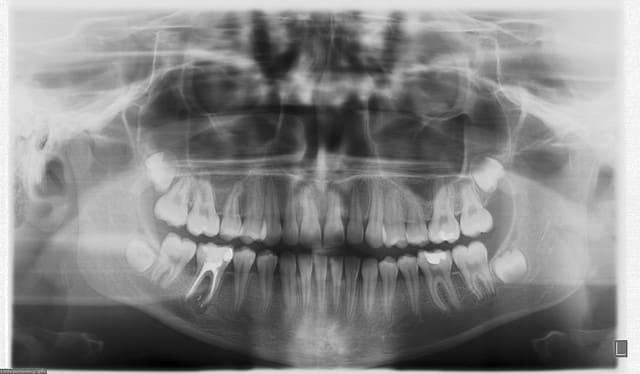

qu'aurais-tu fait de la 46...

patiente de 13 ans qui vient me consulter pour ODF...cl1 ddm

fistule vestibulaire...mobilité3...

voilà la radio 6 mois plus tard....

Ne jamais sous-estimer le potentiel de guérison des enfants...

Pour l'odf...je viens de lui poser son multibagues cet AM...pour la suite...contrôles radios durant tout le traitement ODF...en cas de problème...je tracterai la 47...mais je me dis que si je n'avais pas au moins essayé...j'aurais peut-être mutilé cette gamine pour rien...

il n'y a plus de fistule...la mobilité est redevenue normale...la radio montre clairement une reconstruction osseuse...c'est pas encore parfait...mais çà m'a l'air en très bonne voie...le TR à été terminé il y a 3 mois...

bravo mais ....à suivre:)

radio ds 6 mois?:)

ds ton pronostic d'odf,les 48/18 auront t'elles la place de se mettre en normoclusion?

c'est souvent ce que je discute avec l'odf:si la 8 doit être extraite plus tard,je préfère une 7 en 6 et une 8 en 7 qu'une 6 traitée à couronner,à condition que ce soit gérable mais là la balle est ds son camp

à priori...les 8 ont la place...dans ce cas on est en ddm positive (trop de place)

Radio dans 6 mois en effet....